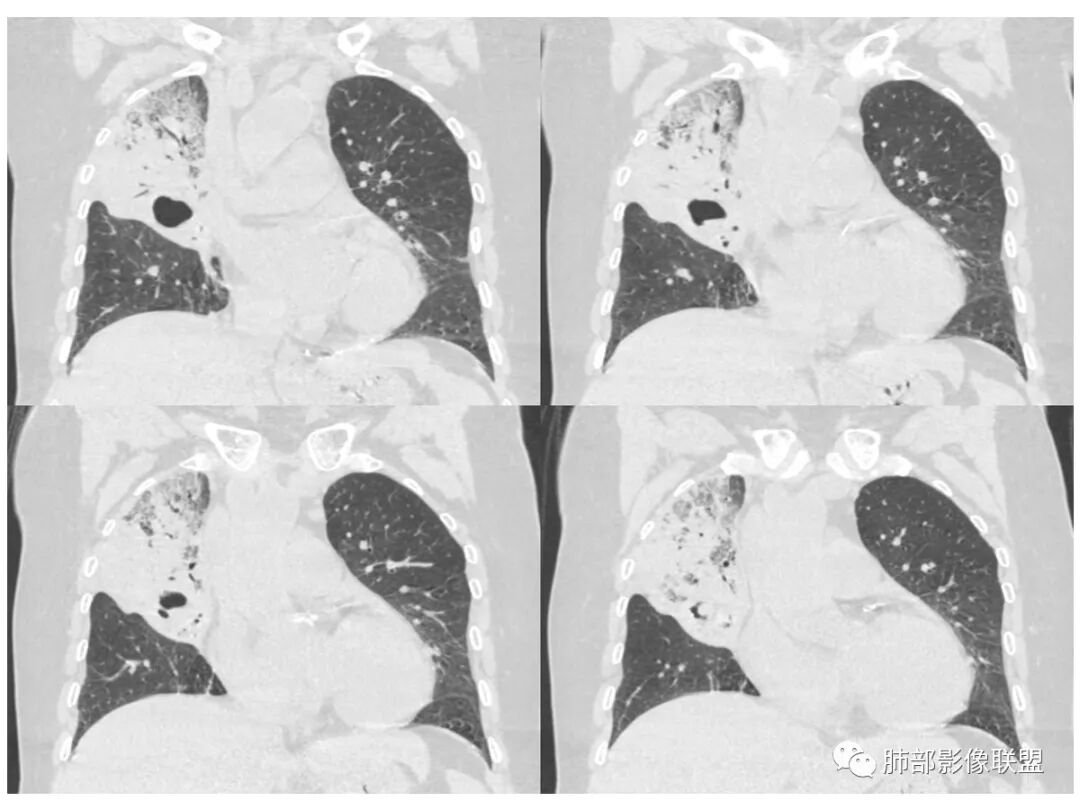

右肺上叶大片状阴影,内见僵硬的支气管,部分支气管轻度扩张,内见一空洞和液平,病灶边缘可见磨玻璃影,首先考虑恶性病变,粘液性腺癌伴感染可能。

老年女性,右肺上叶大片实变及磨玻璃密度影,磨玻璃边缘清晰,内可见小叶间隔增厚,内可见空洞,似可见分隔,叶间裂局部膨隆,纵膈窗,没有增强,枯树枝不明显,肺炎型肺癌可能,鉴别大叶性肺炎,结核?

胸CT:右肺上叶实变内可见支气管充气征,近端支气管狭窄,远端扩张,周围可见毛玻璃影,右肺中叶支气管闭塞,并可见气道壁钙化,右肺中叶体积缩小,实变内可见空洞,并可见气液平面,空洞周围可见毛玻璃样影,右肺下叶支气管开口狭窄,右肺门淋巴结肿大。纵隔窗可见病灶与壁层胸膜间隙增宽,考虑良性病变-----感染性病变------TB?

病史老年女,白痰;影像实变,ggo多数边界清,病灶下缘部分不清,枯树枝,支气管近端阻塞、僵硬,病灶跨叶;病灶内空洞,有液平;间质增厚有结节感;肺炎型肺癌大于干酪性肺炎。

老年女性,慢性病程,咳嗽伴白色粘液痰,无发热腹痛,糖尿病,白细胞及C反应蛋白不高,血沉快,铁蛋白高。胸部CT,右肺上叶大片状实变伴磨玻璃密度影,边界不清,边缘局部膨隆,叶裂弧形下坠,实变影宽基底与胸膜相贴;右肺下叶前基底段见类似病灶;右肺中叶不张并空洞形成,空洞内见气液平面;综合考虑右肺上叶及下叶肺炎型肺癌,右肺中叶结核。

老年女性,病史1月,右肺上中叶大片状影,跨叶,上叶为主,磨玻璃为主,边界模糊,部分实变,内见空洞影和液气平面,壁光滑,支气管开口狭窄,局部有扩张,右肺门淋巴结钙化,首先考虑感染性病变,结核可能,鉴别粘液腺癌。

患者老年女性,亚急性起病,胸部CT:右肺上叶大片实变,可内见坏死性空洞,可见mGGO,GGO边缘清晰,局部彭隆,内见支气管充气征,可惜没增强,粘液腺癌要考虑,但病灶明显是内朝外不支持,综合考虑结核,建议查痰找抗酸杆菌、气管镜

老年女性,咳白色粘液痰,右肺跨叶大片高密度影,密度不均匀,其内见支气管枯树征,有空洞,边缘部分清楚,叶间裂有下坠膨隆感。考虑粘液腺癌,鉴别干酪性肺炎